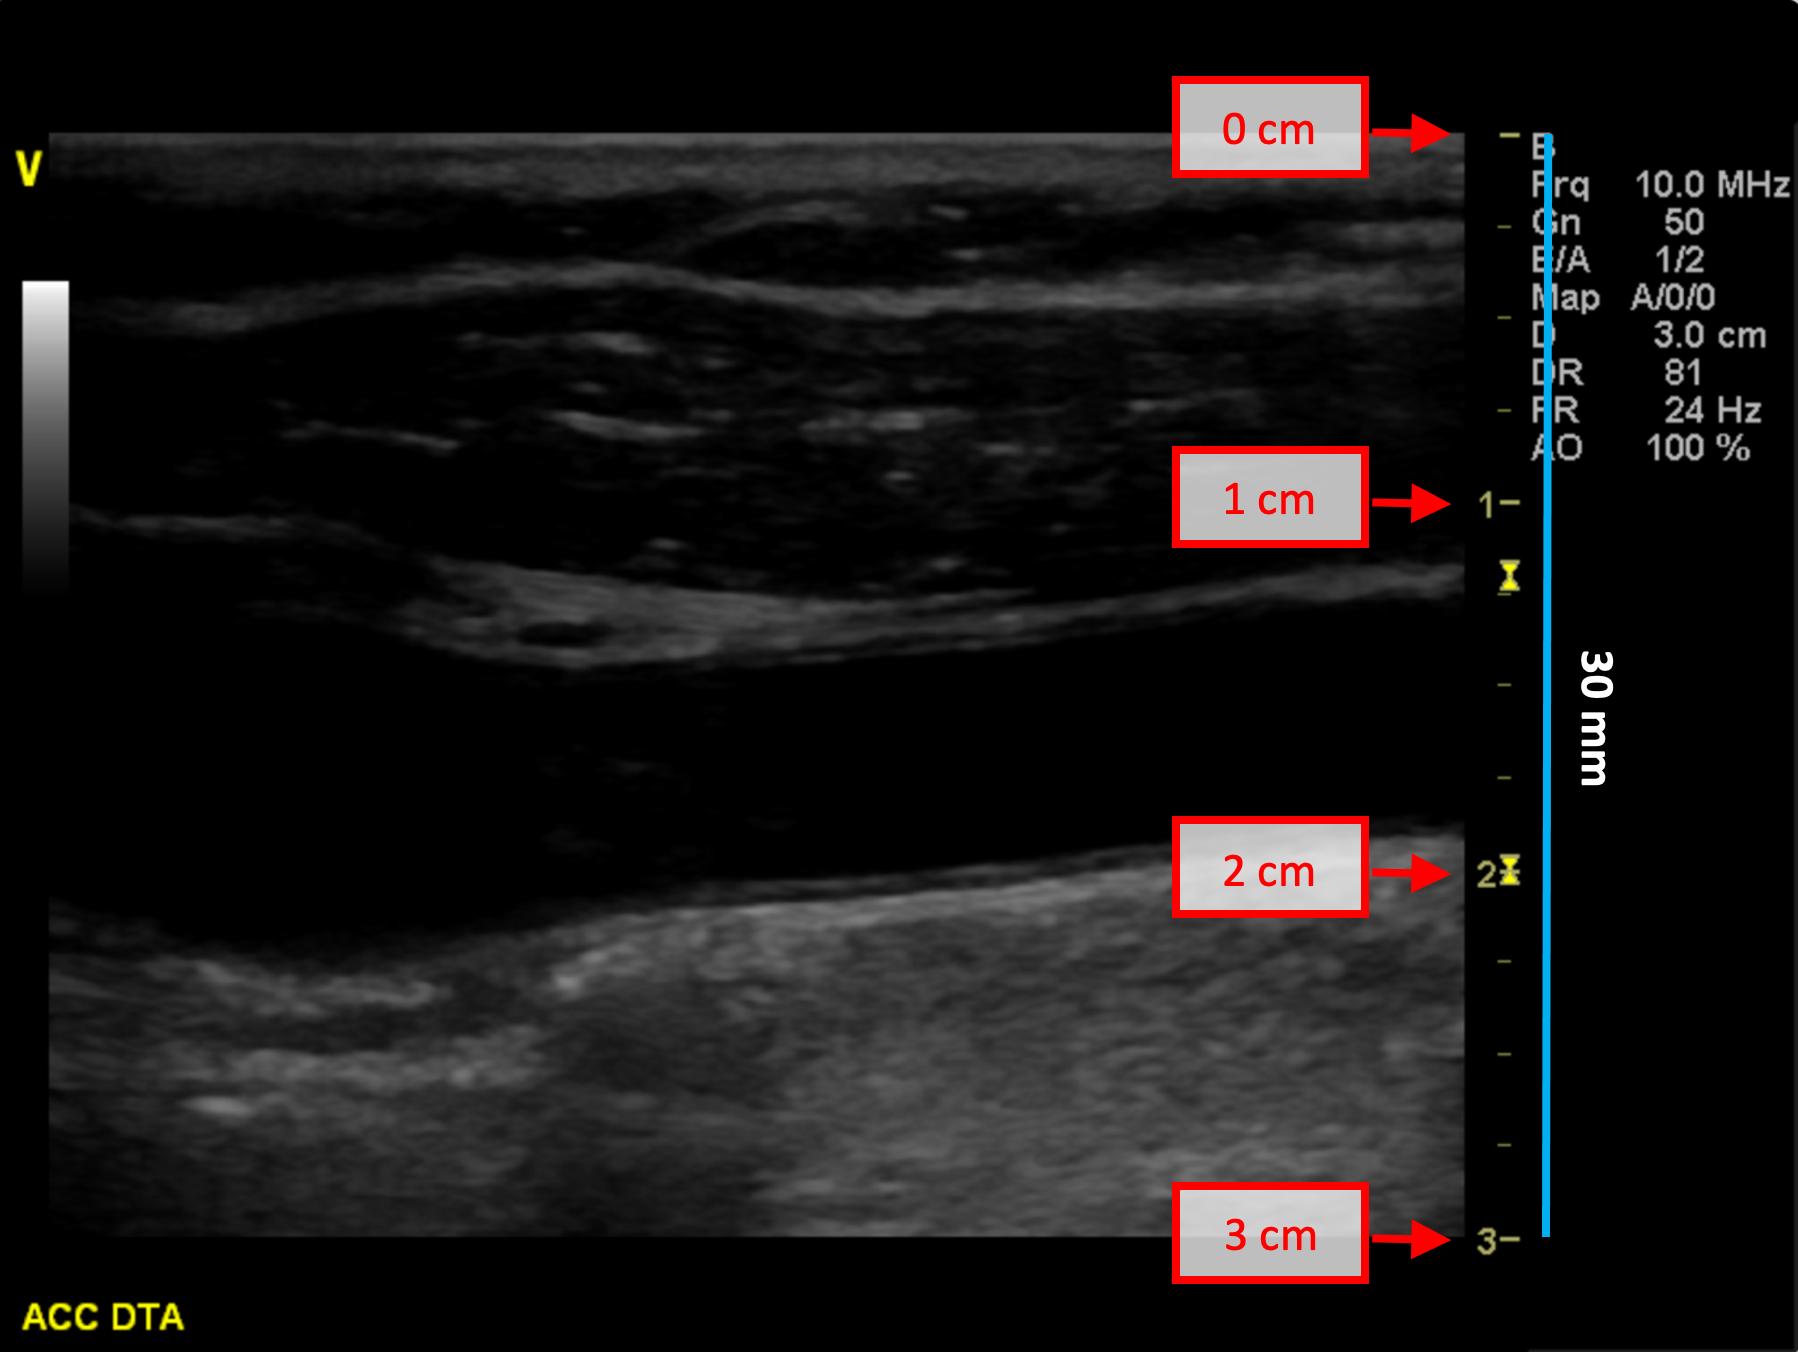

B-mode calibration examples

The following images show examples of calibrations of the b-mode image. Graphic items in red shows where you can find the information about the depth of the image in the ultrasound image.